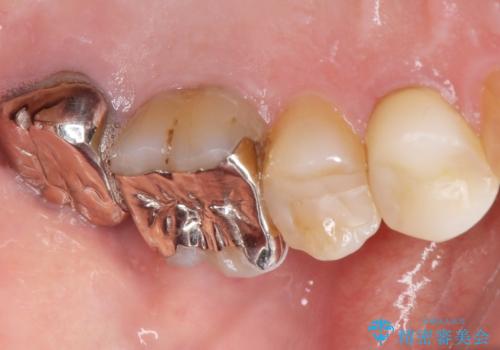

- 歯ぐき(ちょうど根の先のあたり)から膿が出て、根の治療を何度しても治らないことを主訴に来院された患者様です。

精査したところ、奥歯(左上67)の根尖部に位置した歯茎に瘻孔(膿の出口)ができており、CTを撮影し確認すると奥歯2本(左上67)の根尖病変は大きくつながっていました。